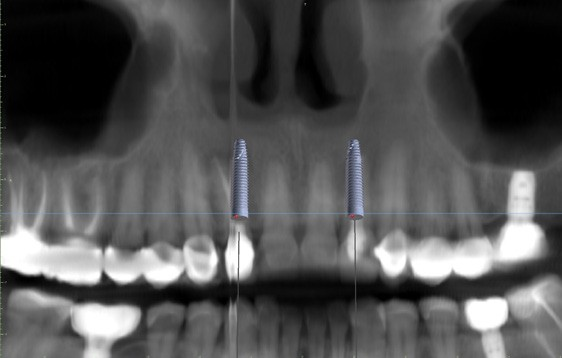

Upon prosthetic evaluation, since bothteeth were deemed unrestorable, the replacement plan an implant supported restoration. Radiographically, tooth #7 exhibited a moderate-sized periapical radiolucency.During the initial examination appointment, a CBCT and I-tero scans were obtained along with the appropriate shade to start planning an immediate non-functional tem-porary restoration. An intraoral scan was sent to the lab for digital planning of the temporary restorations.

A CBCT review showed adequate bone palatal to the socket wall, so the bone density appeared to be favorable for immediate implant placement.